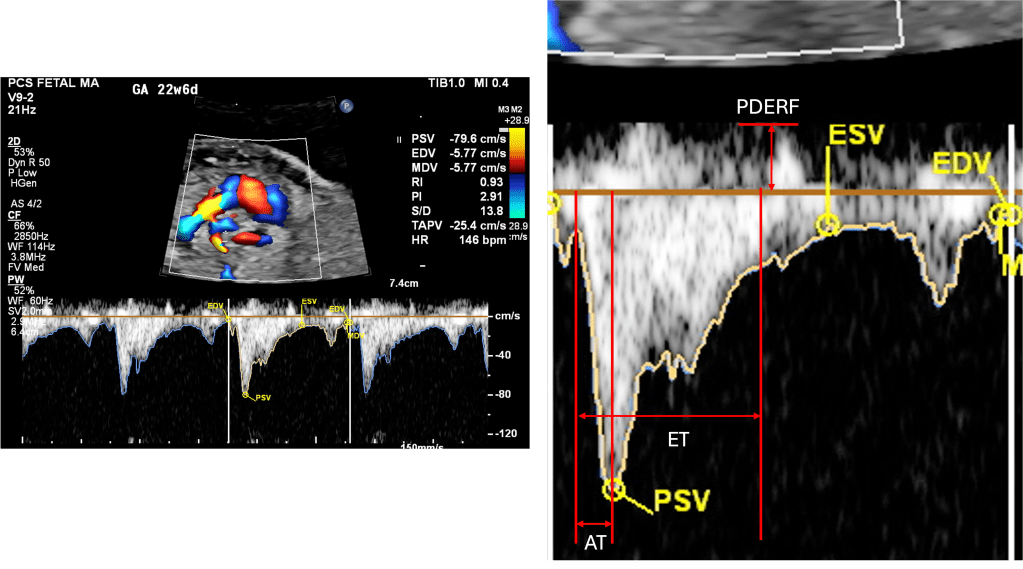

PSV – Peak Systolic Velocity

- The highest point of the systolic wave.

- Reflects the strength of proper ventricular systolic ejection into the branch PA.

AT – Acceleration Time

- Interval from the onset of forward flow to the peak systolic velocity.

- Sensitive to pulmonary vascular resistance (PVR).

ET – Ejection Time

- Duration of forward flow from onset to end of systolic ejection.

- Prolongs slightly with gestation; provides denominator for AT/ET ratio.

EDV – End-Diastolic Velocity

- Velocity of forward flow at the end of diastole.

- Usually slight but forward (positive).

- Absent or reversed EDV is abnormal, suggesting high downstream resistance.

PEDRF – Peak Early Diastolic Reversed Flow

- A brief negative deflection after systole (just below baseline).

- Commonly seen in fetuses, not pathologic if mild.

- Excessive or persistent reversal may suggest abnormal impedance in the distal pulmonary vasculature.

PI – Pulsatility Index

- Calculated as: PI = {PSV – EDV}/Mean velocity

- A measure of downstream resistance.

- High PI → high resistance (e.g., CDH, pulmonary hypoplasia).

- Low PI → lower resistance, as lungs mature or after maternal oxygen.